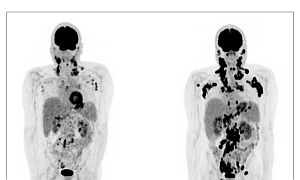

Az orvos a korábban sikeresen kezelt, gyógyultnak tekintett bélrákos eseteknél agresszív, több területet érintő kiújulásokat észlelt, szokatlan áttétekkel, mint pl. egy kóros felkarcsonttörés, ahol a daganat elpusztította a felkarcsont fejet.

Középkorú és idős emberek jelentkeznek nála agresszív, 4. stádiumú kolorektális rákkal, akik gyógyíthatatlanok, és heteken vagy hónapokon belül meghalnak. Sok esetben az egész májat nagy kerek daganatok töltik ki. Tapasztalatai szerint a vastagbélrák időseknél ritkán ennyire agresszív; általában véletlenül derül fény rá, és eltávolítható.

A közelmúltban három olyan beteget látott, akinél 2 különálló bélrák alakult ki egyidejűleg a vastagbél különböző területein. Ez korábban ritka volt (<3%).